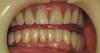

johniola Опубликовано 17 июня, 2013 Поделиться Опубликовано 17 июня, 2013 Как и обещал .Пациентка 68 лет, 6 лет назад были установлены 4 импланта и съёмный протез на локаторах.Женщина курящая,гигиена на 3+. 4 Ссылка на комментарий